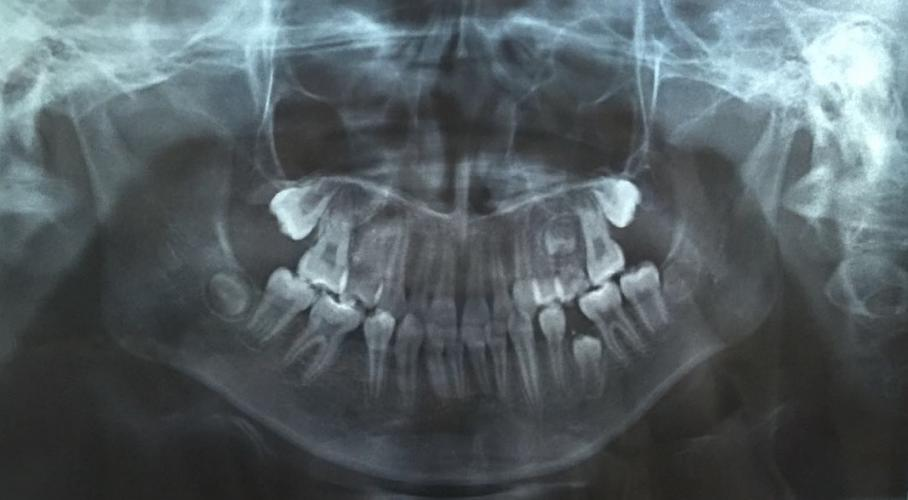

圖片由院方提供

兒童口腔科副主任醫(yī)師王銳副教授為琦琦拍攝了一張曲面斷層片,發(fā)現(xiàn)琦琦左下后牙區(qū)有一顆牙齒因間隙不足阻生,建議家長接受矯正調(diào)節(jié),擴開間隙,觀察阻生于頜骨內(nèi)的牙齒是否可以順利萌出。調(diào)節(jié)過程相對復雜,調(diào)節(jié)周期較長,需要每隔一個月復診一次?!昂⒆咏衲晟铣踔?,課業(yè)壓力越來越大,但既然牙齒出現(xiàn)這么嚴重的問題,擠時間也要積極配合醫(yī)生調(diào)節(jié)?!泵鎸@種情況,琦琦媽媽無奈的說。

據(jù)王銳副教授介紹,孩子的乳牙脫落要及時到醫(yī)院拍攝曲面斷層片觀察是否存在乳牙早失、恒牙阻生或發(fā)育異常等情況,一旦發(fā)現(xiàn)乳牙早失必須及時制作間隙保持器保留牙齒間隙,給恒牙足夠的萌出空間,避免嚴重后果。